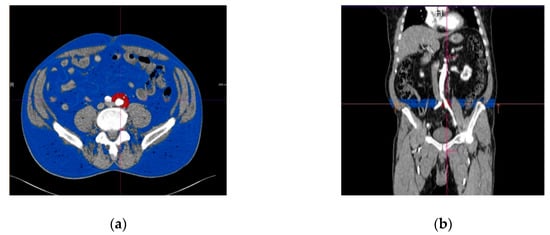

The volume of the PIAT was measured for both the right and left common iliac arteries, along the whole vessel and on each slice. The border of the PIAT was manually traced around the vessel, throughout the whole length of the iliac arteries, at a limit of 2 cm from the vessel border. After opening the imaging acquisition with the dedicate postprocessing software, a circle was manually traced around the target common iliac artery. The traced circle was manually adjusted in order to mark the tissues correctly around the vessel, at 2 cm outwards from the vascular wall. The following step included manual delineation of the circular border of the vessel at the bifurcation of the common iliac artery. The postprocessing software allowed automatic interpolation of the contours in a longitudinal direction on the examined segments and measurement of the perivascular adipose tissue using a color-coded system for a superior representation (Figure 2a,b). The software automatically detects the volume of the periiliac adipose tissue (with a CT attenuation ranging between −150 to −50 HU) after interpolation of contours, with a color-coded display. The volume of the perivascular adipose tissue was automatically calculated and displayed expressed in milliliters and with red color. The subcutaneous and visceral adipose tissue are represented with blue color.

Figure 2.

Perivascular adipose tissue surrounding left common iliac artery (marked in red color). (a) Transverse section; (b) longitudinal section, with the region of interest immediately after the origin of the iliac arteries from the aorta. The subcutaneous adipose tissue is represented in blue.

To determine the volume of the subcutaneous and visceral adipose tissue at the whole length of the chosen common iliac artery, we used the function of automated interpolation of contours to create the separation line on the anterior and posterior abdominal muscles at the whole length of the vessel, as presented in Figure 3. The volume of the subcutaneous and visceral adipose tissue was then determined automatically and displayed together with the ratio between them. Figure 4 illustrates a diagram of the image postprocessing steps.

Figure 3.

Subcutaneous and visceral adipose tissue determined with angio CT (computed tomography angiography), measured at the level of the origin of the right common iliac artery. (a) Transverse view, (b) longitudinal view. The visceral adipose tissue is represented in red, while the subcutaneous adipose tissue is represented in blue.